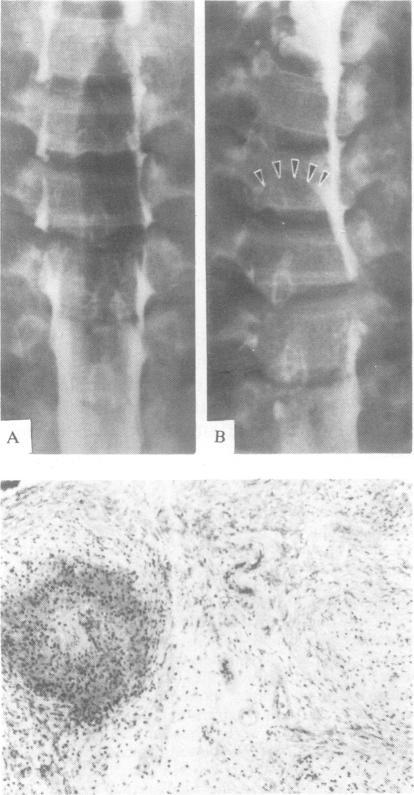

A 26-year-old male with a history of pulmonary sarcoidosis showed clinical, myelographic and intra-operative evidence of a C5-C6 spinal cord tumour, which was diagnosed by biopsy as a pure intramedullary granuloma. Among the 29 published cases of histologically proven cord sarcoidosis, only five presented with pure parenchymatous infiltration without meningeal involvement. Corticosteroids are the most useful therapy, and surgery is indicated only for minimal biopsy when the parenchyma is invaded.

一名26岁有肺结节病病史的男性,有临床、脊髓造影及术中证据显示存在C5 - C6脊髓肿瘤,经活检诊断为单纯髓内肉芽肿。在29例经组织学证实的脊髓结节病已发表病例中,只有5例表现为单纯实质浸润而无脑膜受累。皮质类固醇是最有效的治疗方法,仅在实质受侵犯时为进行最小限度活检才考虑手术。